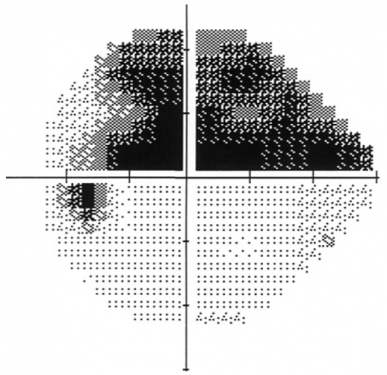

Visual field test

This test involves bright and dim lights shone in your peripheral vision - you will be asked to click a button each time you see a light. This is used to generate a map of peripheral vision for each eye. It can detect loss of peripheral vision from glaucoma that may not be obvious to you. It can also be used to monitor for change in glaucoma over time.

Visual field test result